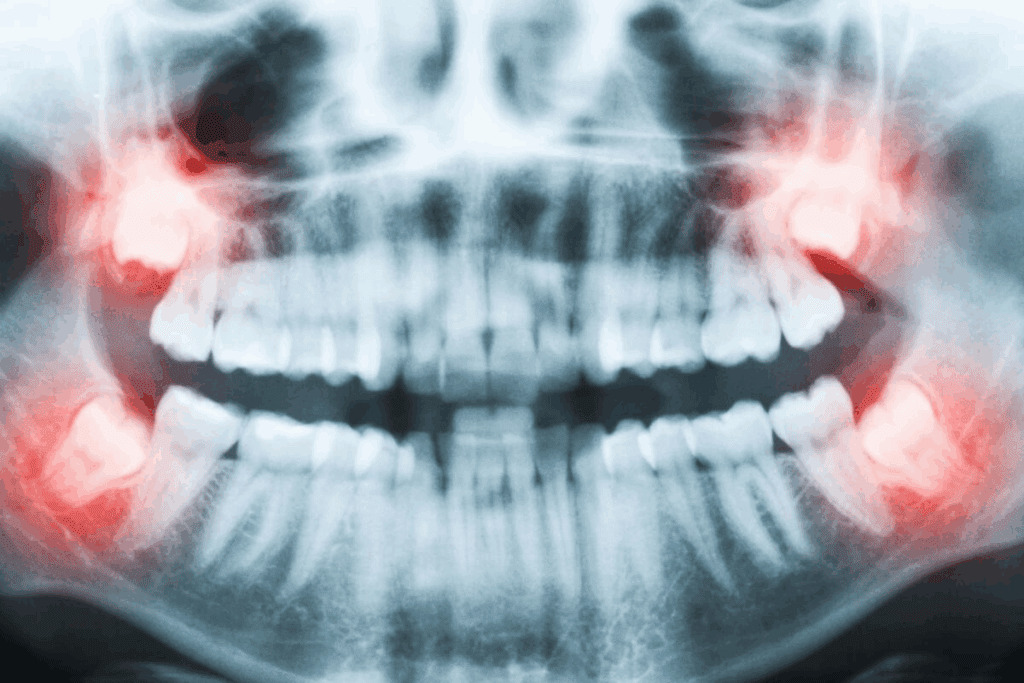

Potential Risks and Complications: What Patients Should Know

It’s important for patients to know about the risks and complications of dental implants. Dental implants are usually safe, but it’s good to know about possible problems. These can happen during or after the procedure.

Surgical Risks During Placement

The surgery to place dental implants can have risks like other surgeries. These risks include:

- Infection at the implant site

- Nerve damage causing pain, numbness, or tingling

- Bleeding or hematoma formation

- Damage to surrounding teeth or structures

Choosing an experienced dental surgeon is key. They should use the latest techniques and follow strict infection control.